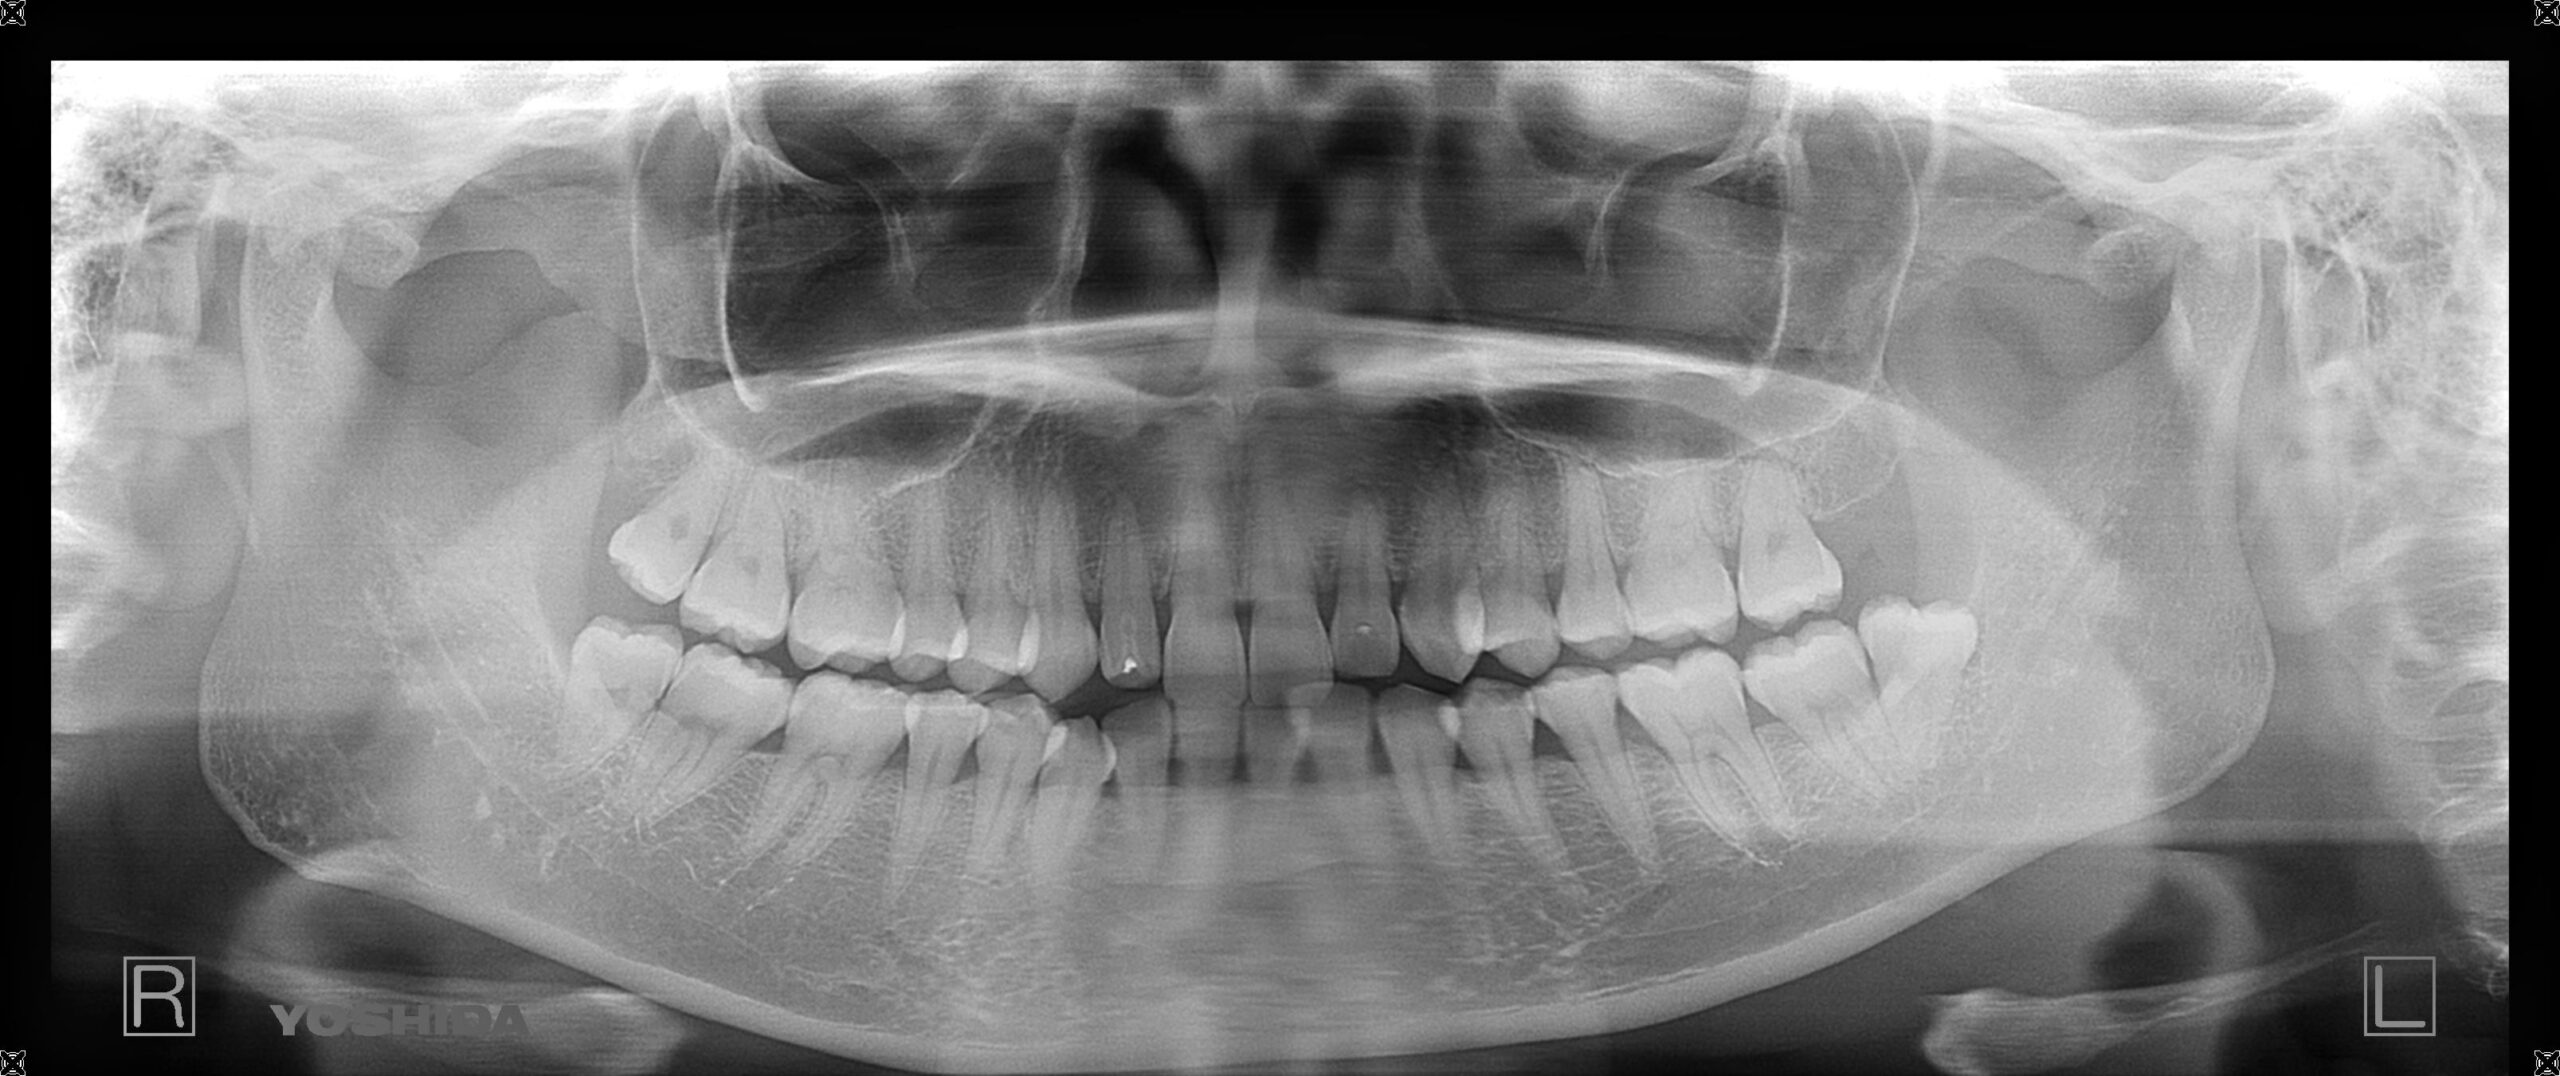

Before